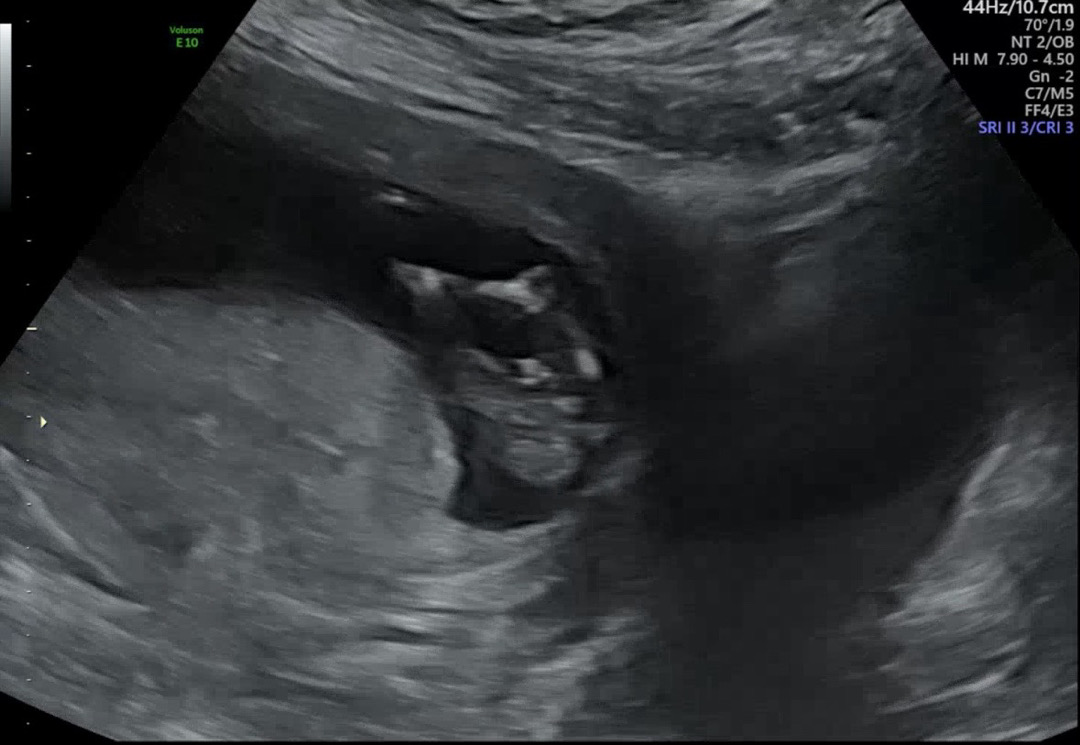

12주 5일차애기 가랑이사이🌶️일까요?

뭐가 자꾸 보이는데 🌶️ 일까요 아니면 다른게 착시처럼 보이는걸까요? 제발 고수님들 도와주세요ㅜㅜ

음.. 삼각점 보이는 것 같긴한데.. 4주만 더 기다려보아요 ㅠㅠ